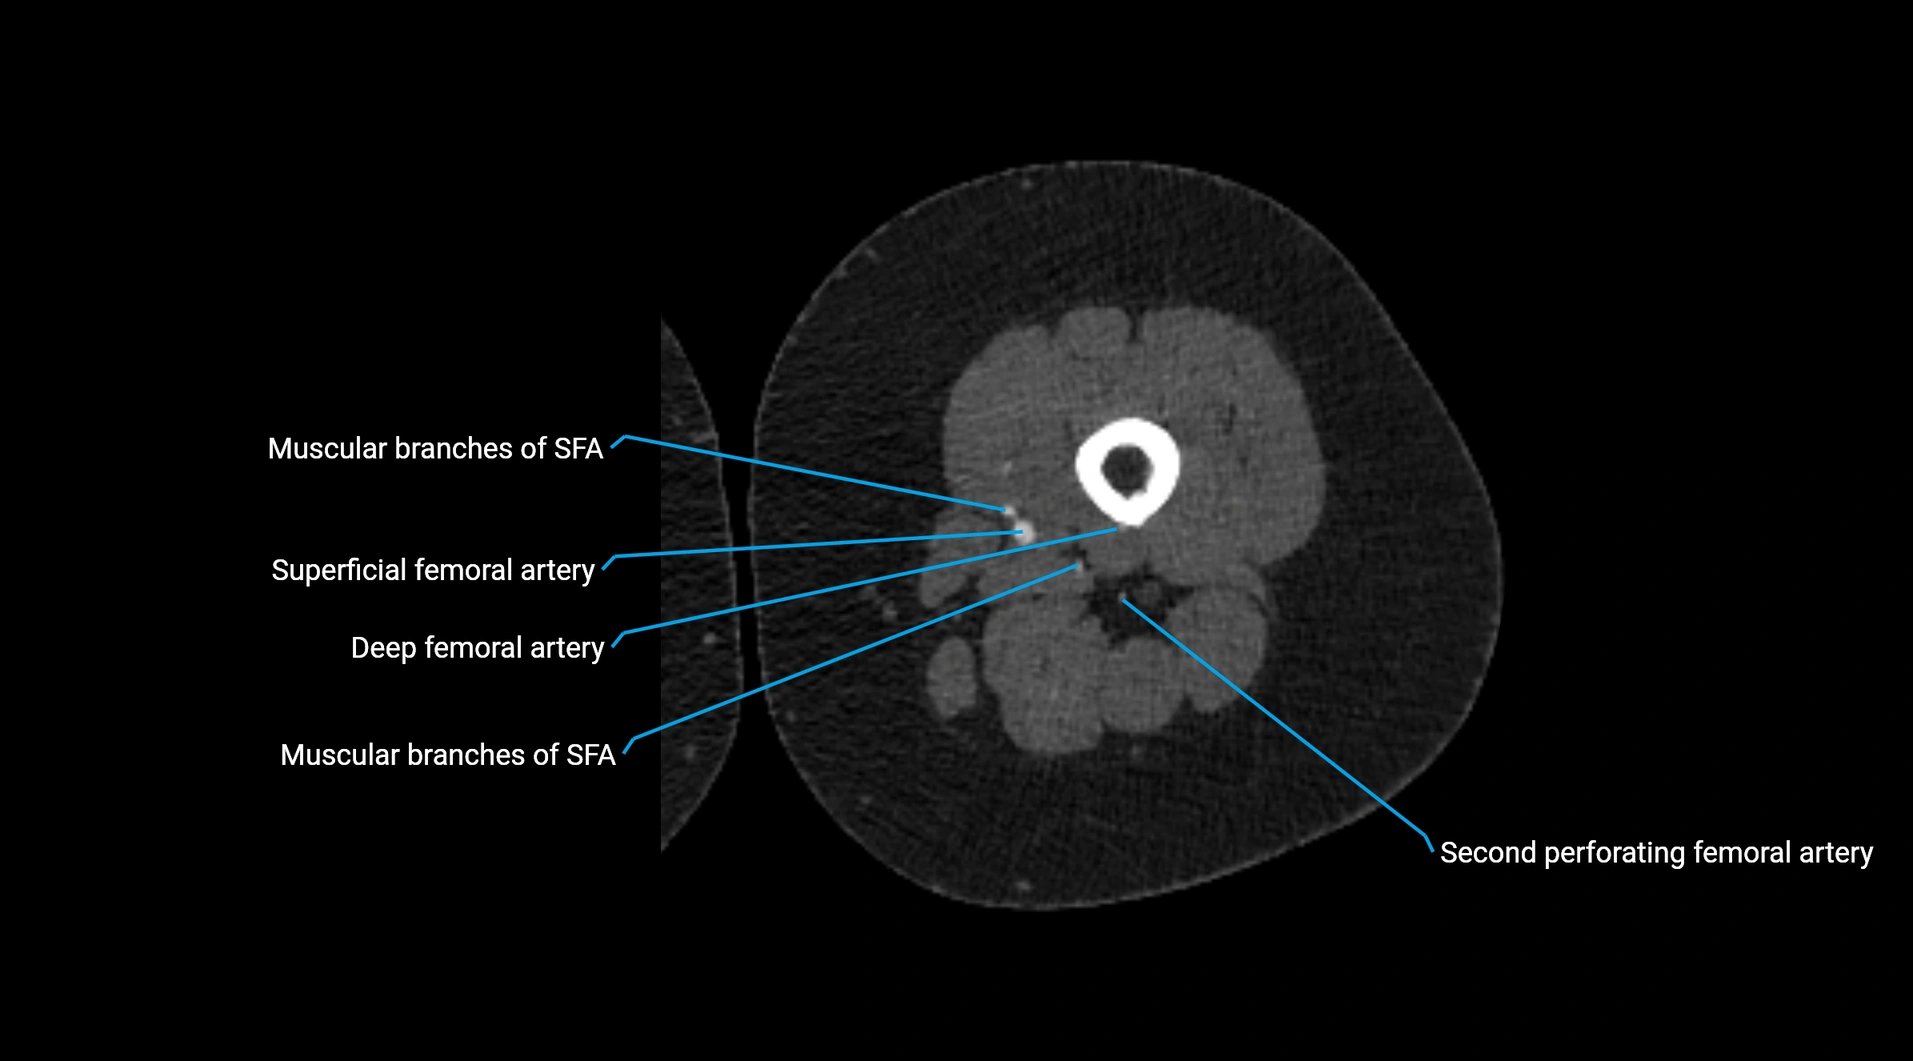

CT images

image

Contrast-enhanced CT (CTA):

• Gold standard for abdominal aortic imaging

• Provides excellent detail of lumen, wall, aneurysm, thrombus, and branch vessels

• Multiplanar and 3D reconstructions help in aneurysm measurement, stent graft planning, and dissection evaluation

• Detects acute rupture, traumatic injury, or occlusion with high sensitivity